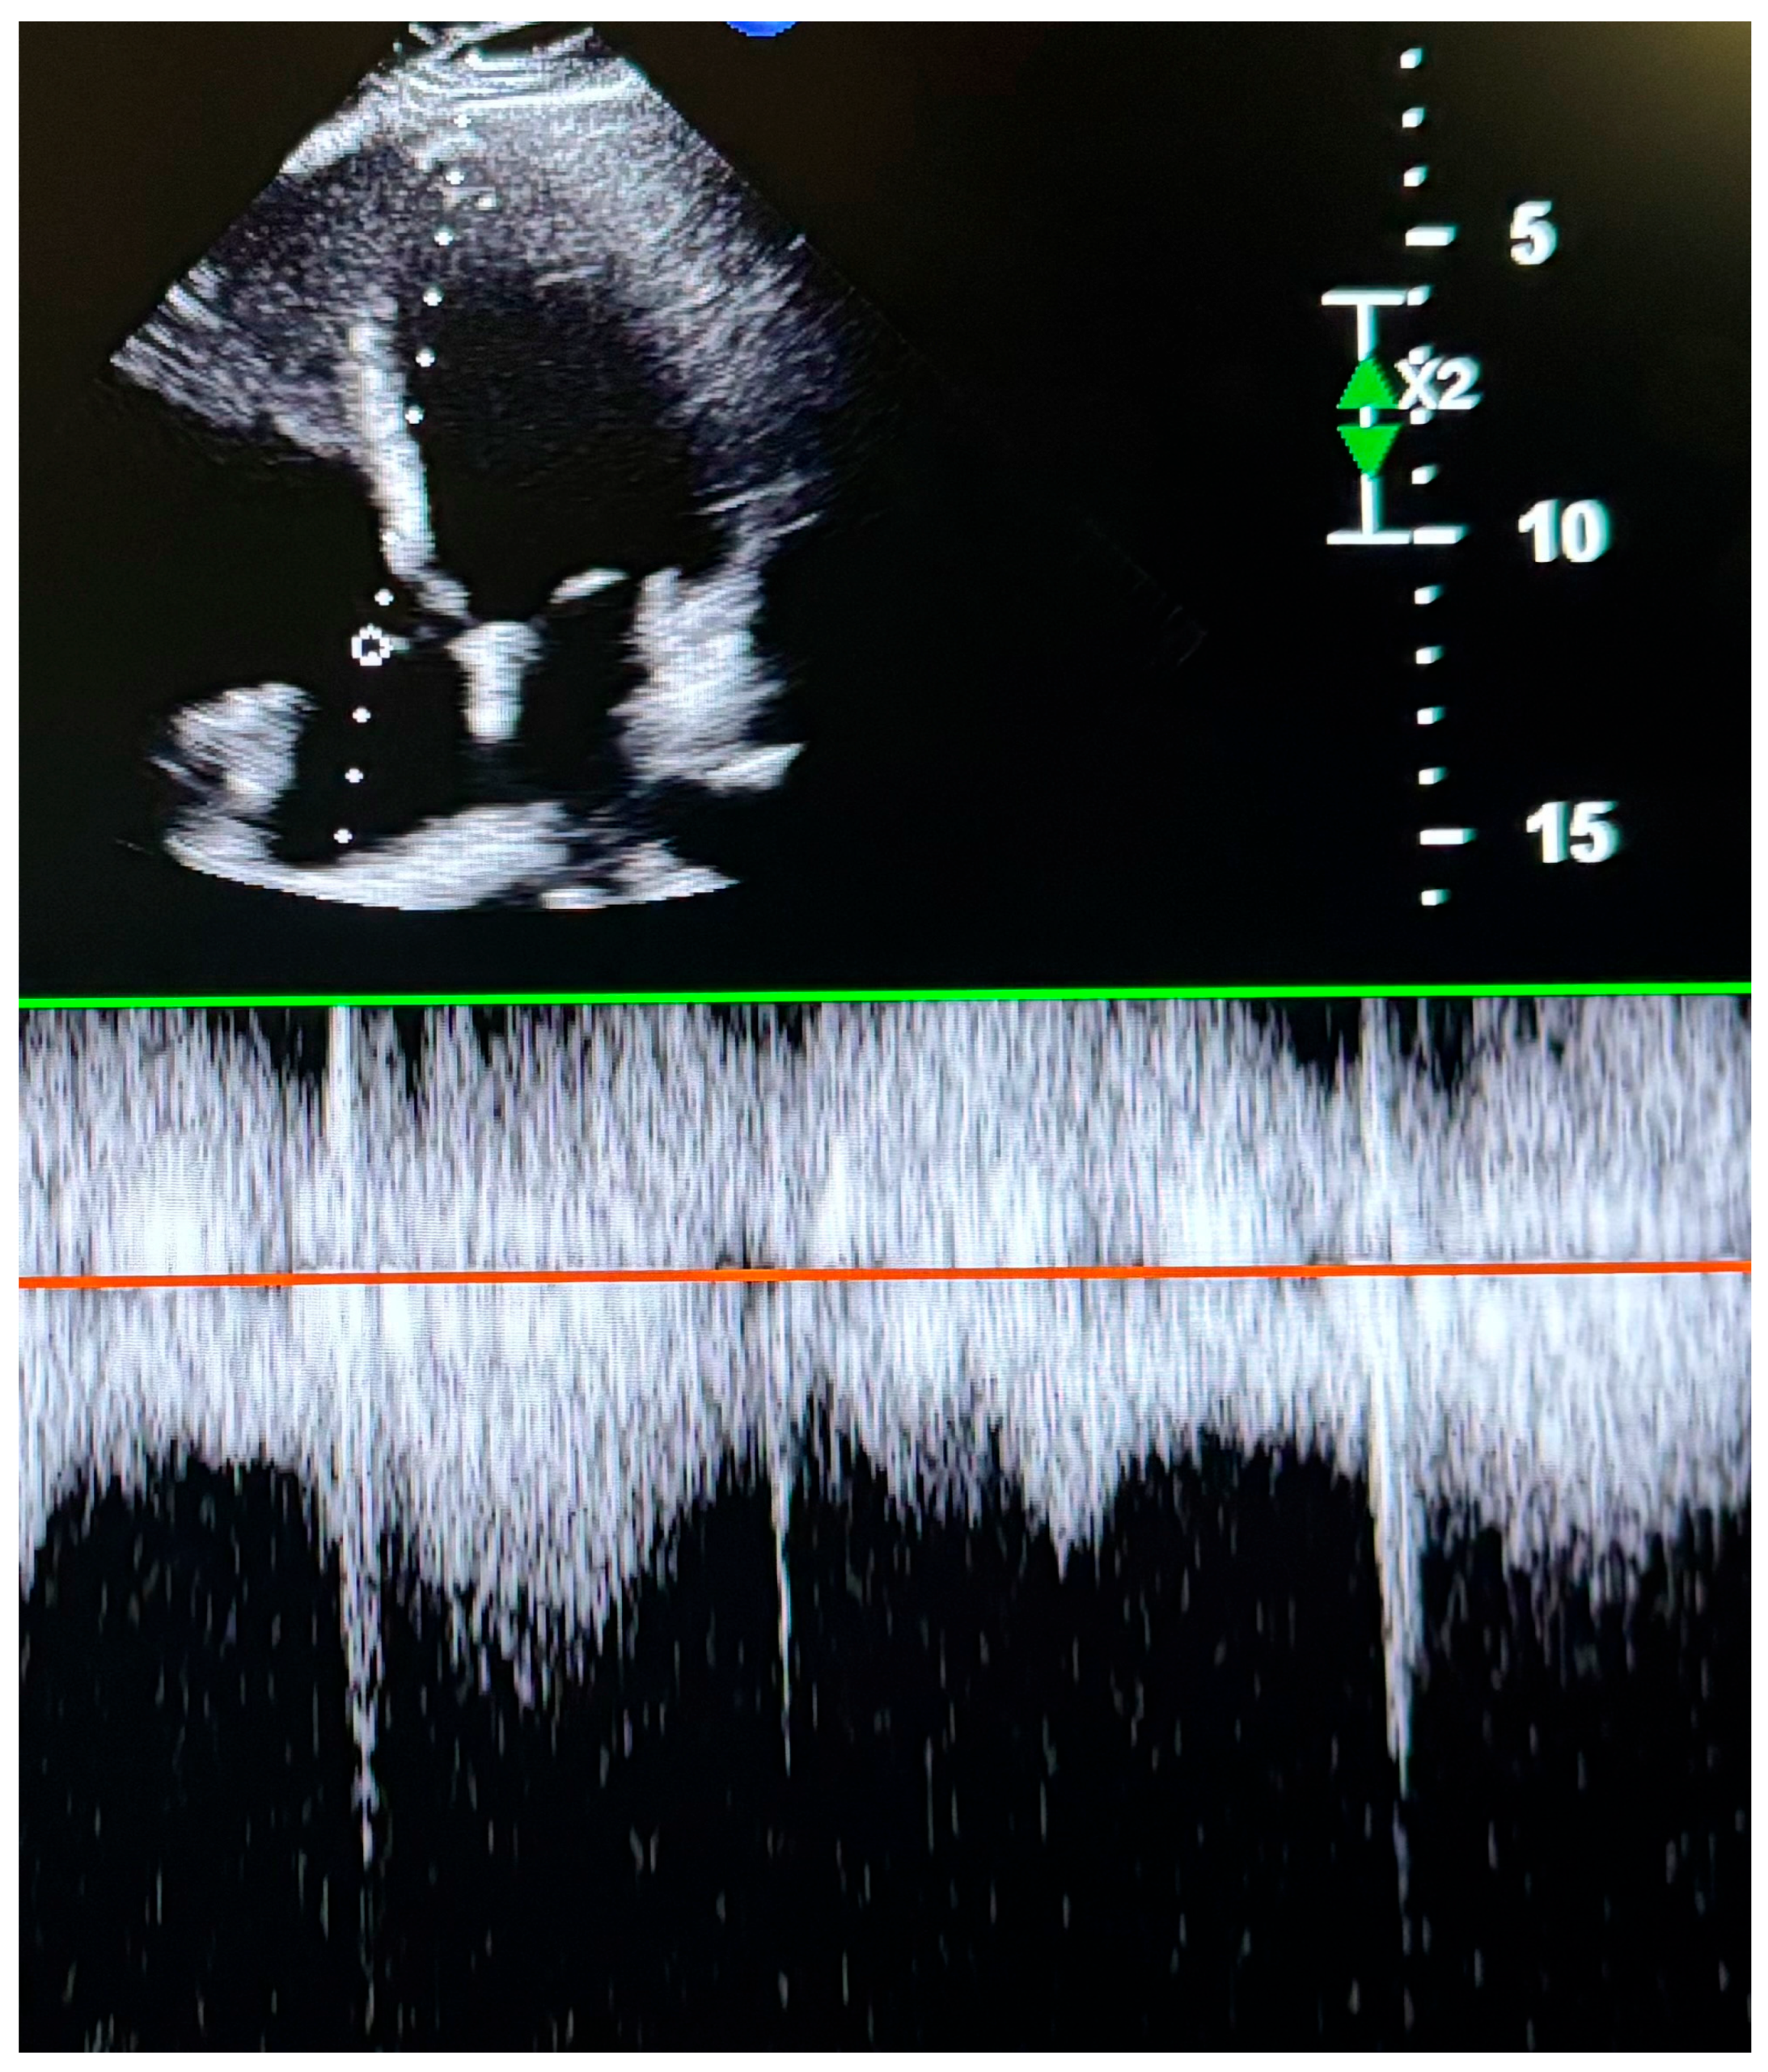

To assess RV systolic function, myocardial performance index (MPI), fractional area change (FAC), TAPSE, and TDI-derived indices were measured. RV diastolic function was evaluated using tricuspid E and A wave velocities and the E/A ratio. TAPSE was obtained by placing an M-mode marker along the tricuspid annulus and measuring its longitudinal motion at peak systole. Ejection time (ET), isovolumetric relaxation time (IVRT), and isovolumetric contraction time (IVCT) were derived from TDI images. The MPI was calculated as a global index of RV function using the formula MPI = (IVCT + IVRT)/ET. Tricuspid regurgitation (TR) was assessed using color Doppler interrogation in the apical four-chamber view. A well-defined continuous-wave (CW) Doppler TR signal was obtained for the accurate determination of the peak tricuspid regurgitant velocity (TRV) (Figure 2). IVC measurements were performed in the supine position using a subxiphoid approach. The cursor was placed 1 cm distal to the hepatic vein–IVC junction, and the IVC diameter was monitored for 30 s in M-mode. Measurements were recorded at peak inspiration (IVCins) and peak expiration (IVCexp) during normal breathing (Figure 3). The IVC collapsibility index (IVC-CI) was calculated using the formula: IVC-CI = (IVCexp − IVCins)/IVCexp.

Figure 2. Transthoracic echocardiographic image showing tricuspid peak velocity.